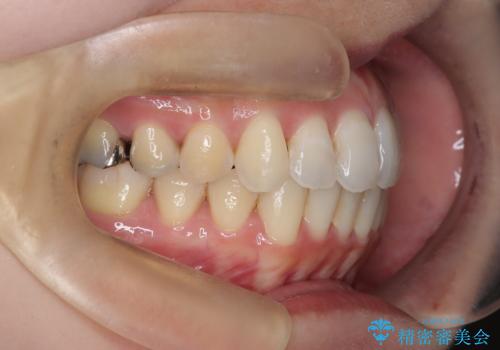

- 前歯のガタガタを主訴に来院された患者様です。

前歯の傾きも少し内側に入るように計画をたて、インビザラインにて治療を行いました。

このぐらいのガタガタであれば、インビザラインで簡単に治すことができます。